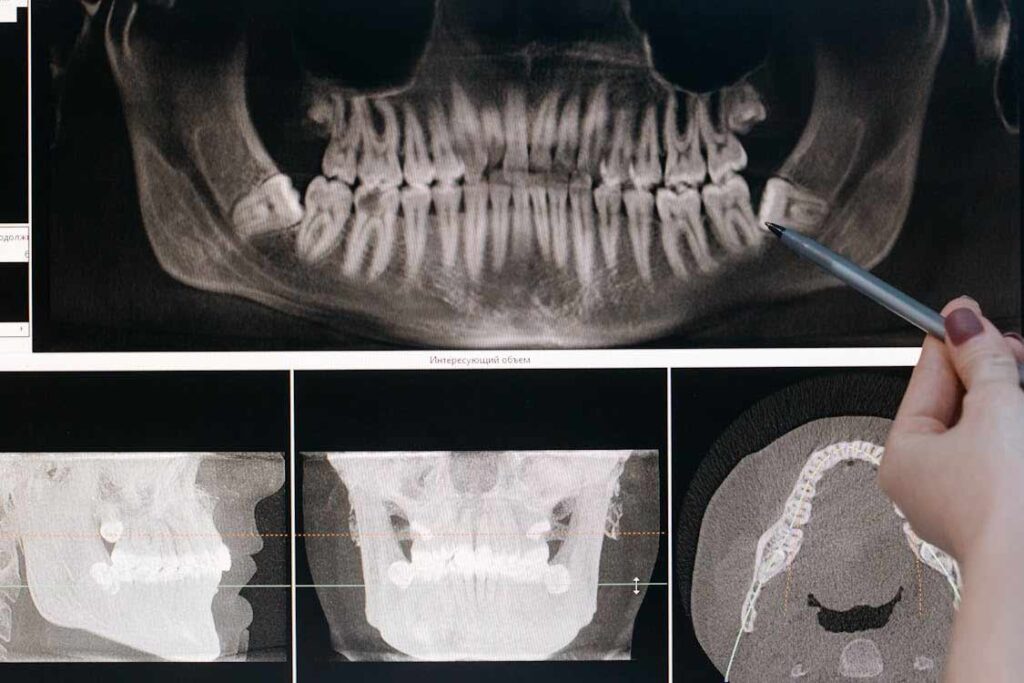

- Focused exam and X-ray to check position (erupted vs. impacted).